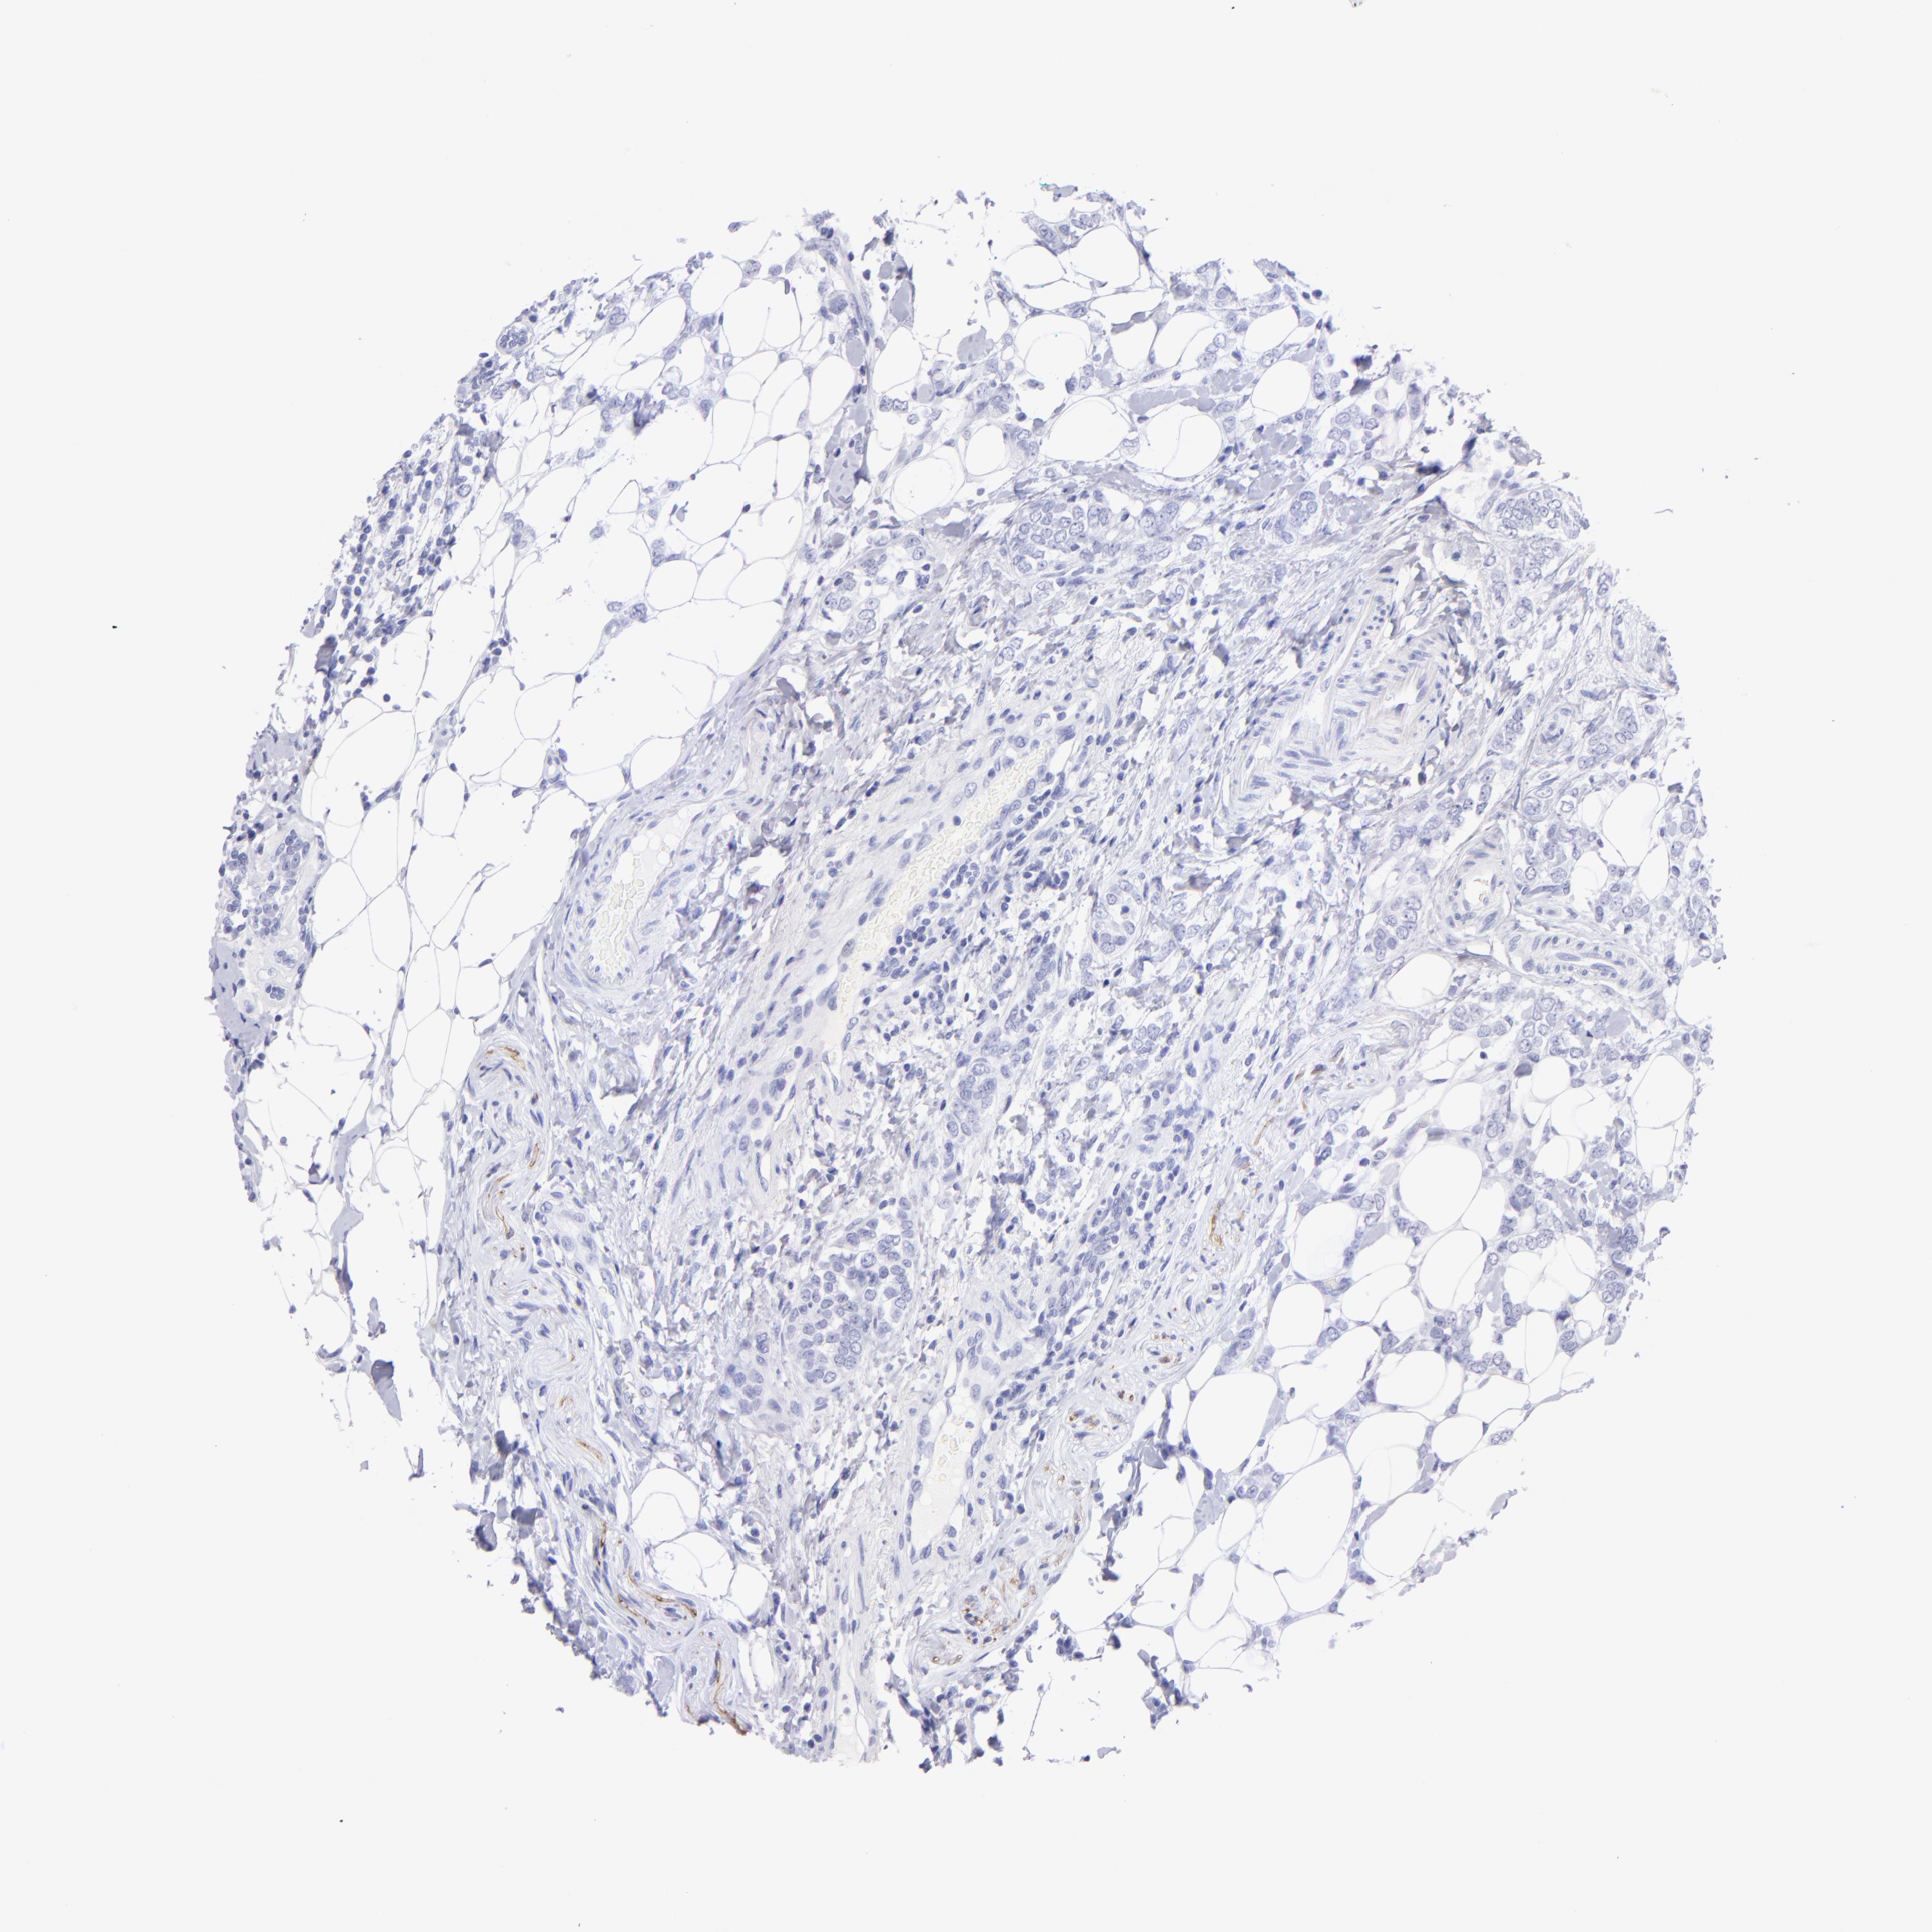

CANCER BREAST CANCER Show tissue menu

Breast cancer

Human cancer